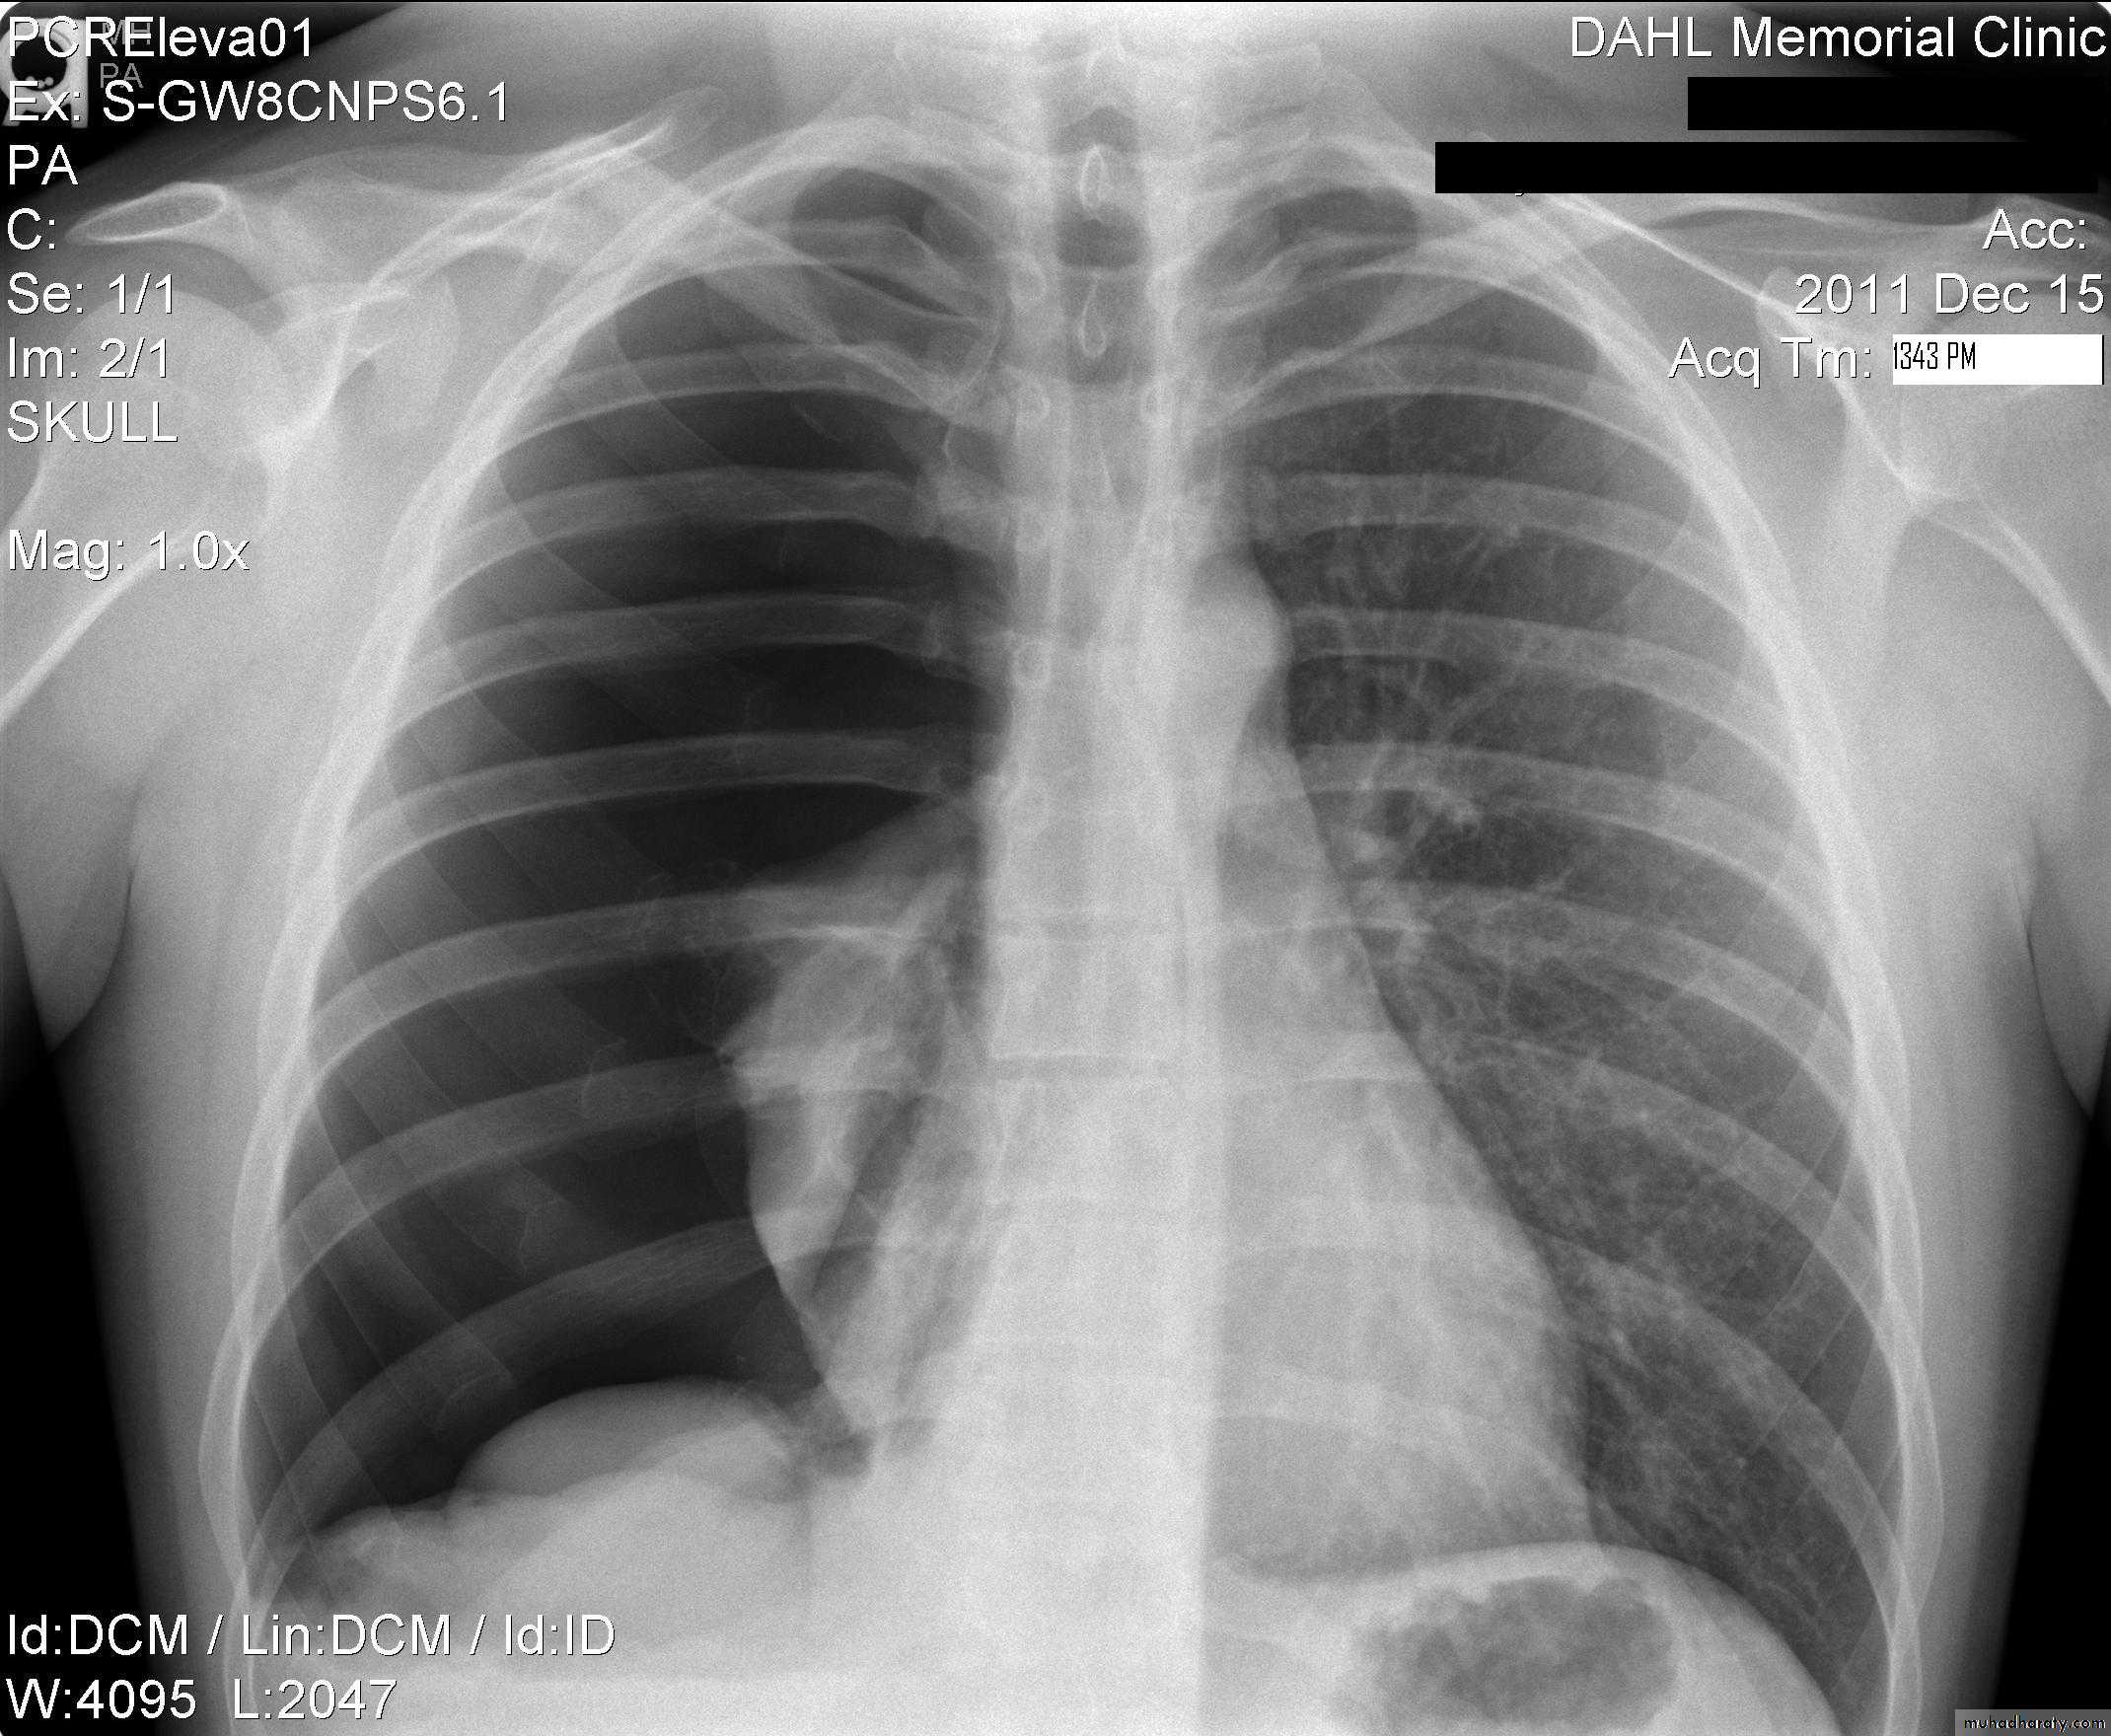

Pleural effusion

50.pleural effusion

51.pleural effusion .